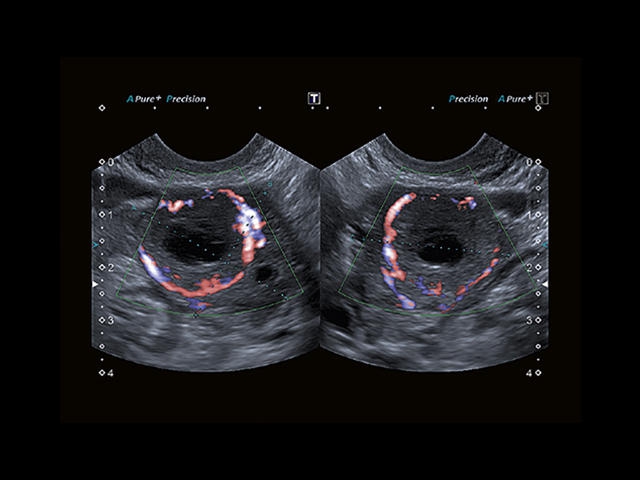

Обновленная версия легендарного УЗ-сканера. Стационарный аппарат экспертного класса Aplio 500 Toshiba NEW, визуализирует анатомические структуры в высоком разрешении. Модель позволяет выявить микрокальцификаты, новообразования, нарушения в работе сердца, сосудов и мышц. Присутствует функция виртуальной эндоскопии, 4D-сканирования, эластометрии тканей, УЗИ с контрастированием. За повышение качества изображения отвечают технологии ApliPure и Superb Microvascular Imaging. Первая задействует возможности пространственного и частотного кодирования, формирует цельный визуальный ряд с сохранением клинических маркеров. Вторая улучшает отображение микрососудистого русла, используя доплеровский эффект. Модель оснащена 21-дюймовым монитором, имеет 4 активных порта. Возможно подключение педиатрических, интраоперационных, лапароскопических и чреспищеводных датчиков.

• SMI. Опция, упрощающая визуализацию микроциркуляторного русла. С ее помощью обследуются сосуды с низкой интенсивностью кровотока, изучаются наиболее тонкие структуры. SMI упрощает диагностику новообразований, минимизирует вероятность ошибки.

Да